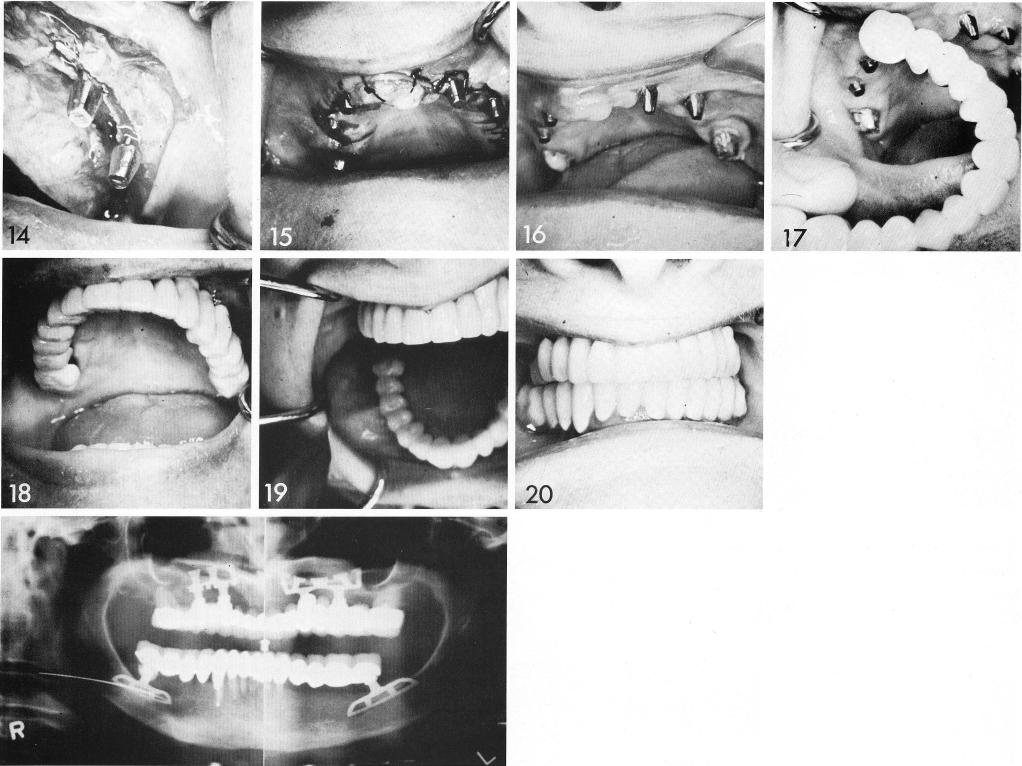

This ridge required considerable work before bladevents could be used. The old appliance (1) was anchored posteriorly bilaterally by a single tooth (2). The revealed ridge was knife-edge (4), with a variety of other flaws, including an unremodeled socket (5). Alveoplasty was in order to smooth socket walls (6) and reduce the knife edge (7,8). This left the residual bone considerably reduced (9). Bladevents were successfully inserted (10-14), and the differences in anterior and posterior abutment height compensated in the prosthesis (19,20).

1 Anterior and posterior maxillary abutments in prosthesis